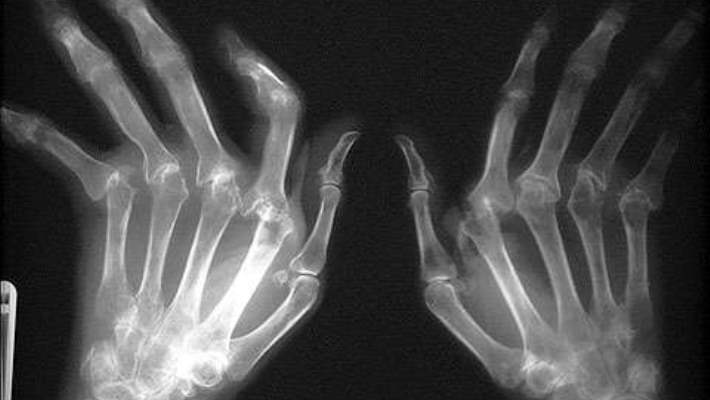

Başlıca belirtileri birkaç eklemde başlayan iltihaplanma nedeniyle oluşan eklemlerde ağrı, şişlik, kızarıklık, uzun süren tutulmalar, halsizlik, yorgunluktur. Fakat daha sonra simetrik ilerleyen bu hastalıkta parmaklarda anormal duruş bozuklukları ve çıkıntılı bir kemik yapıları görülebilir. Hastalığın son evrelerinde göz, kalp, akciğer de etkilenir. Bu noktada kalp zarı ve akciğer zarında iltihaplanmalar, gözde ve ağızda oluşan kuruluk ve baldırda oluşan iltihaplanmalar görülür.